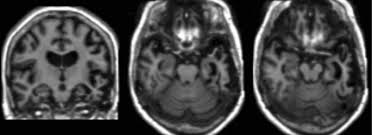

The Radiology Assistant Dementia Role Of Mri

The Radiology Assistant Dementia Role Of Mri from rad.desk.nl

Protein deposits, called lewy bodies, develop in nerve cells in the brain regions involved in thinking, memory and movement (motor control). It's rare in people under 65. Also, there is a helpline for support provided by dementia. Dementia with lewy bodies (dlb), also known as lewy body disease, is a neurodegenerative disease (a synucleinopathy to be specific) related to parkinson disease. Dementia with lewy bodies appears to be the second most common form of dementia, accounting for about one in five cases. Further research is needed to clarify the relationships among them. Some scans (ct and mri scans) look at how the different parts of the brain fit together, rather than how the parts work together. The deposits are called lewy bodies and are named after friedrich h. Dementia is the name for problems with mental abilities caused by gradual changes and damage in the brain. Lewy body dementia, also known as dementia with lewy bodies, is the second most common type of progressive dementia after alzheimer's disease dementia. Certain nuclear scans of the brain, including positron emission. This may include a magnetic resonance imaging (mri) or computed tomography (ct) scan of the brain. After alzheimer disease (ad), dementia with lewy bodies (dlb) is one of the most common types of degenerative dementia.